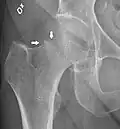

CT scan shows the same, atypical for a fracture since the cortex is coherent -